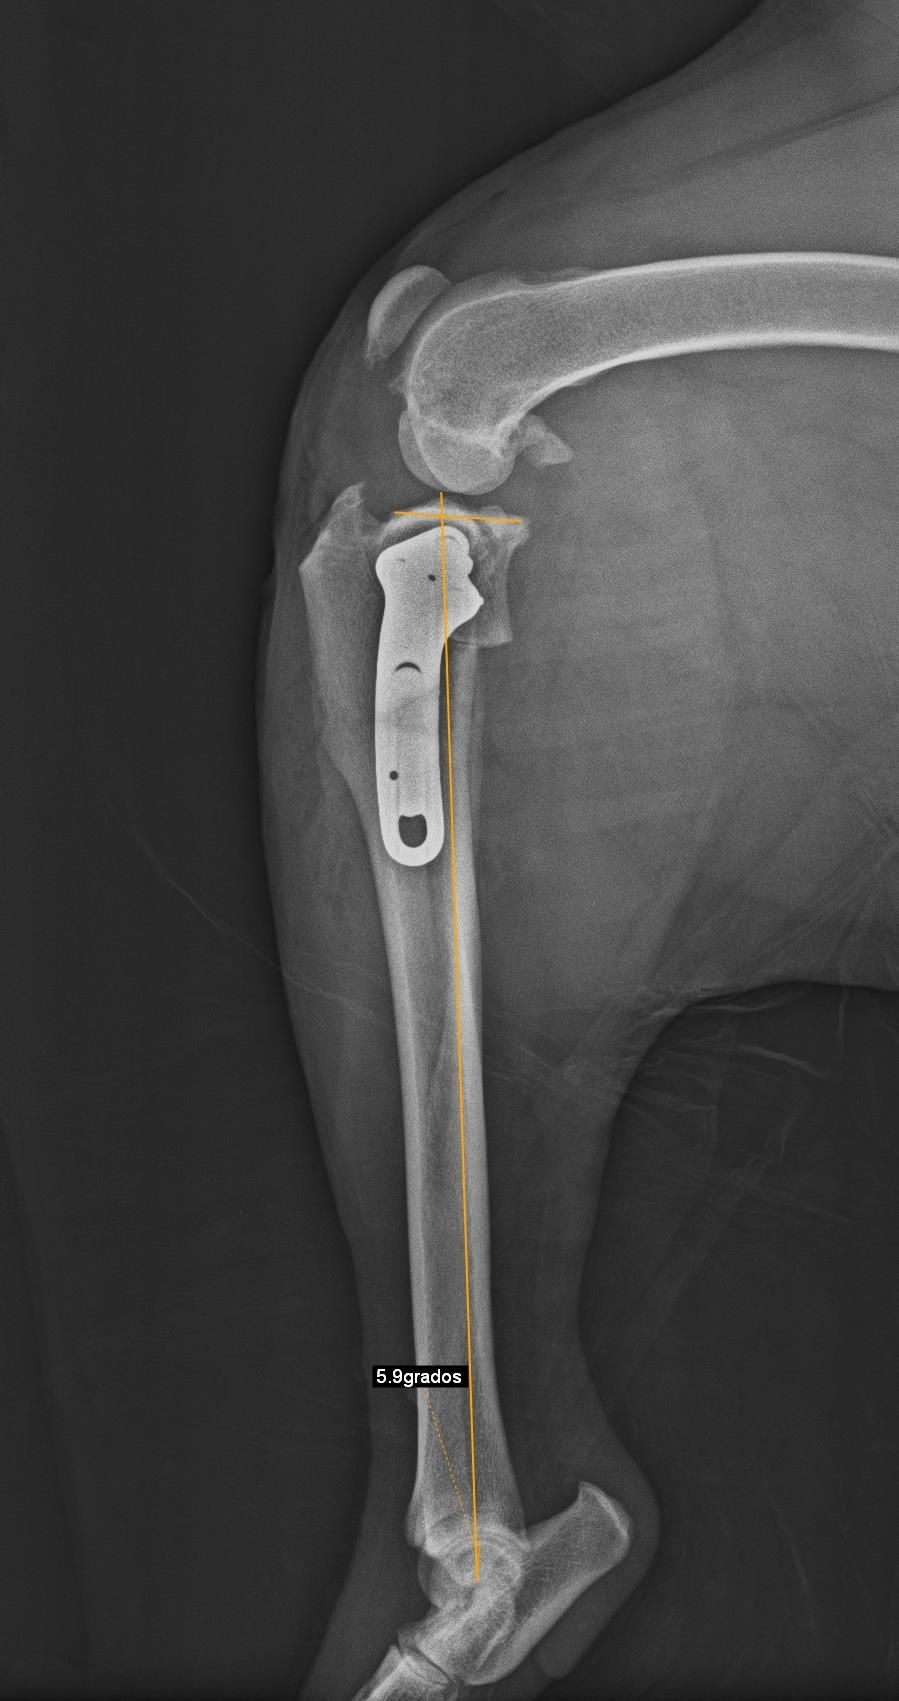

TPLO

La TPLO (Tibial Plateau Levelling Osteotomy) y la TWO (tibial wedge ostectomy) son otras técnicas de resolución de rotura de ligamento cruzado muy eficaces en perros de gran talla.

Consiste en hacer un corte en la tibia y nivelar la meseta tibial, aplicando una placa especial que hace que el ligamento cruzado no sea necesario, ya que se neutralizan la fuerzas de empuje tibial.